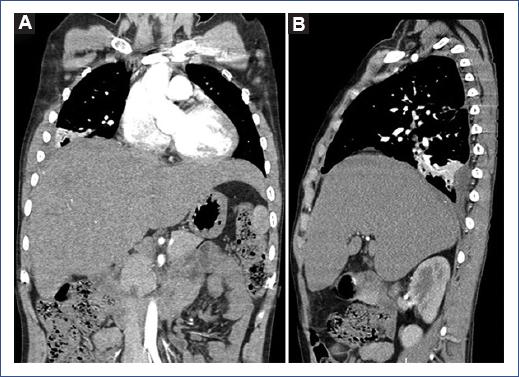

Chest radiography showed complete radiopacity of the right hemithorax with contralateral displacement of the mediastinum. Chest ultrasound showed a heterogeneous encysted accumulation extended over the entire right hemithorax and collapsing the ipsilateral lung. Abdominal ultrasound showed the liver with multiple heterogeneous cystic lesions involving the right lobe without free fluid in the cavity. Thoracic-abdominal tomography showed total right lung atelectasis and massive pleural effusion with a mediastinal shift to the left. In the abdomen, the liver had multiple subdiaphragmatic hepatic collections (the largest measuring 74.3 mm × 82.6 mm × 60.3 mm) with peripheral contrast enhancement in the right hepatic lobe with communication to the right pleural space (Figure 1).

Figure 1 Chest and abdominal tomography. A: coronal plane and B: sagittal plane. Multiple hepatic collections (the largest measuring 74.3 mm × 82.6 mm × 60.3 mm) with diaphragmatic elevation and communication with the right pleural space, associated with hydropneumothorax and total lung collapse.

Diagnostic suspicion arises in residents or persons who recently traveled to regions with relevant epidemiology of parasitic diseases associated with clinical manifestations such as fever, abdominal pain5,9,10, or chest pain with dyspnea11,12 when pulmonary involvement is extensive, as in this patient (Figure 1). Imaging studies, such as ultrasound and tomography, demonstrate cystic intrahepatic cavities and pulmonary involvement, and confirmatory tests, such as serology or antigens, support the diagnosis1.